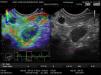

EG-USE cualitativa de ganglio paraesofágico. En la ventana derecha se observa la imagen en escala de grises, un ganglio linfático >1cm, oval, hipoecoico y de bordes bien definidos, y en la izquierda, la misma imagen con la elastografía superpuesta que muestra patrón azul homogéneo (tipo3). En el extremo inferior izquierdo se observa la gráfica de tensión con un recuadro amarillo de la opción «frame average».

El propósito de esta comunicación es mostrar la aplicación de la EG cuantitativa. Presentamos el caso clínico de un varón de 54años referido para estadificación locorregional de carcinoma epidermoide en tercio medio y distal de esófago. Utilizamos un ecoendoscopio lineal electrónico multifrecuencia (EG-3870UTK, Pentax Medical Company, Tokio, Japón) y una consola con EG (AVUIS E 3.5 Hitachi Medical Corporation, Tokio, Japón). Exploramos de manera convencional con modoB identificando 2 GL paraesofágicos distales (estación8) y un tercer ganglio en el axis celíaco, con dimensiones de 10.2×6.7mm, 16.9×11mm y 15.9×9mm, respectivamente, ovales, hipoecoicos y de bordes bien definidos. Activamos la EG, observando una imagen en escala de grises modoB convencional en el lado derecho del monitor, y la misma imagen con la EG superpuesta en el lado izquierdo. Mediante compresión del transductor con apoyo de la gráfica de tensión y considerando los movimientos respiratorios y vasculares se consiguió una imagen estable por aproximadamente 5s, y con la opción «frame average» obtuvimos el mejor fotograma, observando patrón azul homogéneo en los 3 ganglios (fig. 1). Subsecuentemente determinamos el SR; en los fotogramas obtenidos se seleccionó el áreaA (mayor superficie posible del GL) y el áreaB (superficie roja de tejido adyacente normal) (fig. 2), obteniendo valores de 9.83, 19.2 y 13.2, respectivamente. Se realizó BAAF del ganglio celíaco con aguja 22G (Expect™ Boston Scientific) guiada con doppler (fig. 3), un pase que se valoró por citopatólogo determinando muestra adecuada; el resultado citológico definitivo fue carcinoma escamoso metastásico (fig. 4). La estadificación locorregional fue T3 (invasión de la adventicia sin afección de estructuras adyacentes) N2 (3 ganglios incluyendo al celiaco) (AJCC 2010/NCCN2013).